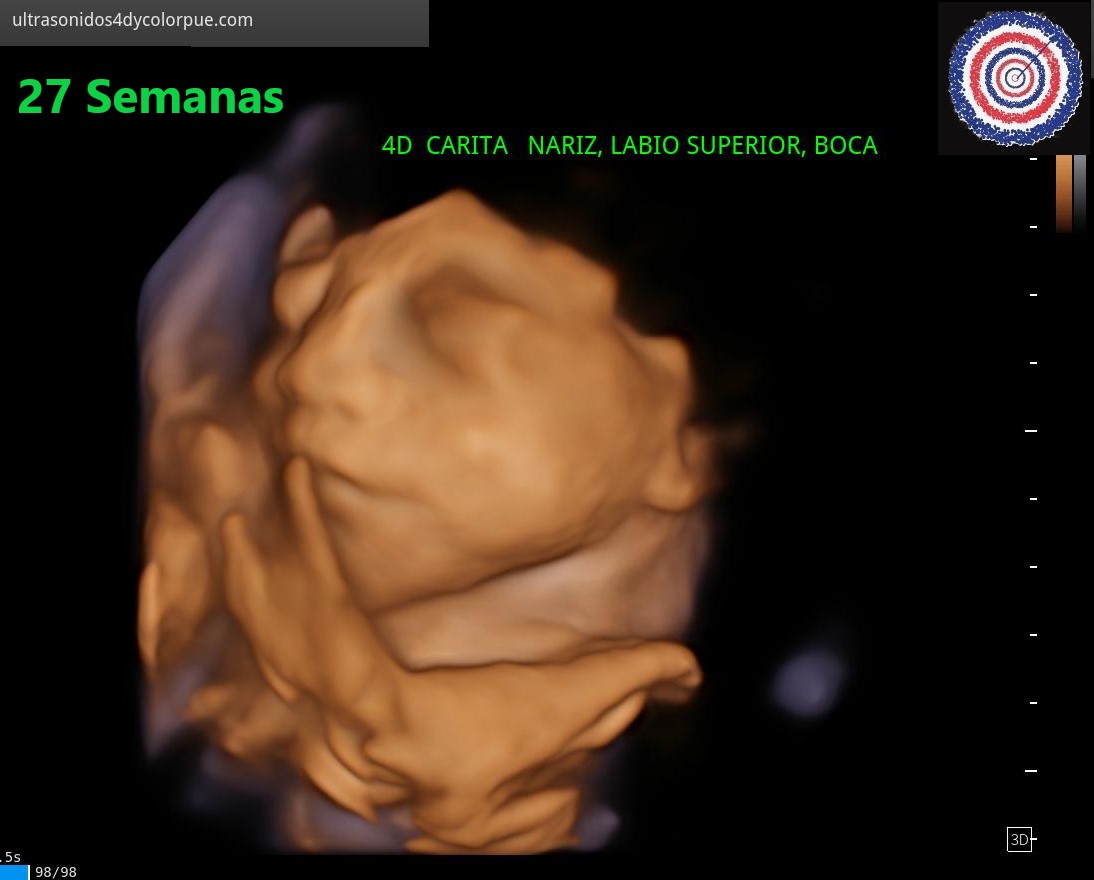

Las imágenes de ULTRASONIDO 3D Y 4D HD LIVE nos permiten realizar observaciones de la cara y el cuerpo que nos aseguran ausencia de anormalidades y al mismo tiempo producen emociones y alegría.